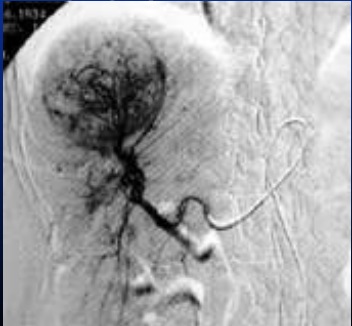

Image de arteriographie d'une

carcinome hepatocellule du foie droit . Aspect

hypervascularisation et de neo vaisseau du tumeur . |